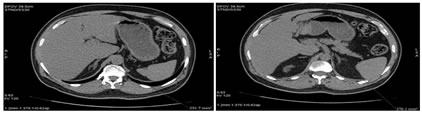

Figure 1: Manual tracing of adrenal gland volume

2a:                                                    2b

Figure 2- 2a: NCCT - Axial section showing Y shaped left adrenal gland; 2b: NCCT – Axial section, showing linear right adrenal gland and triangular left adrenal gland